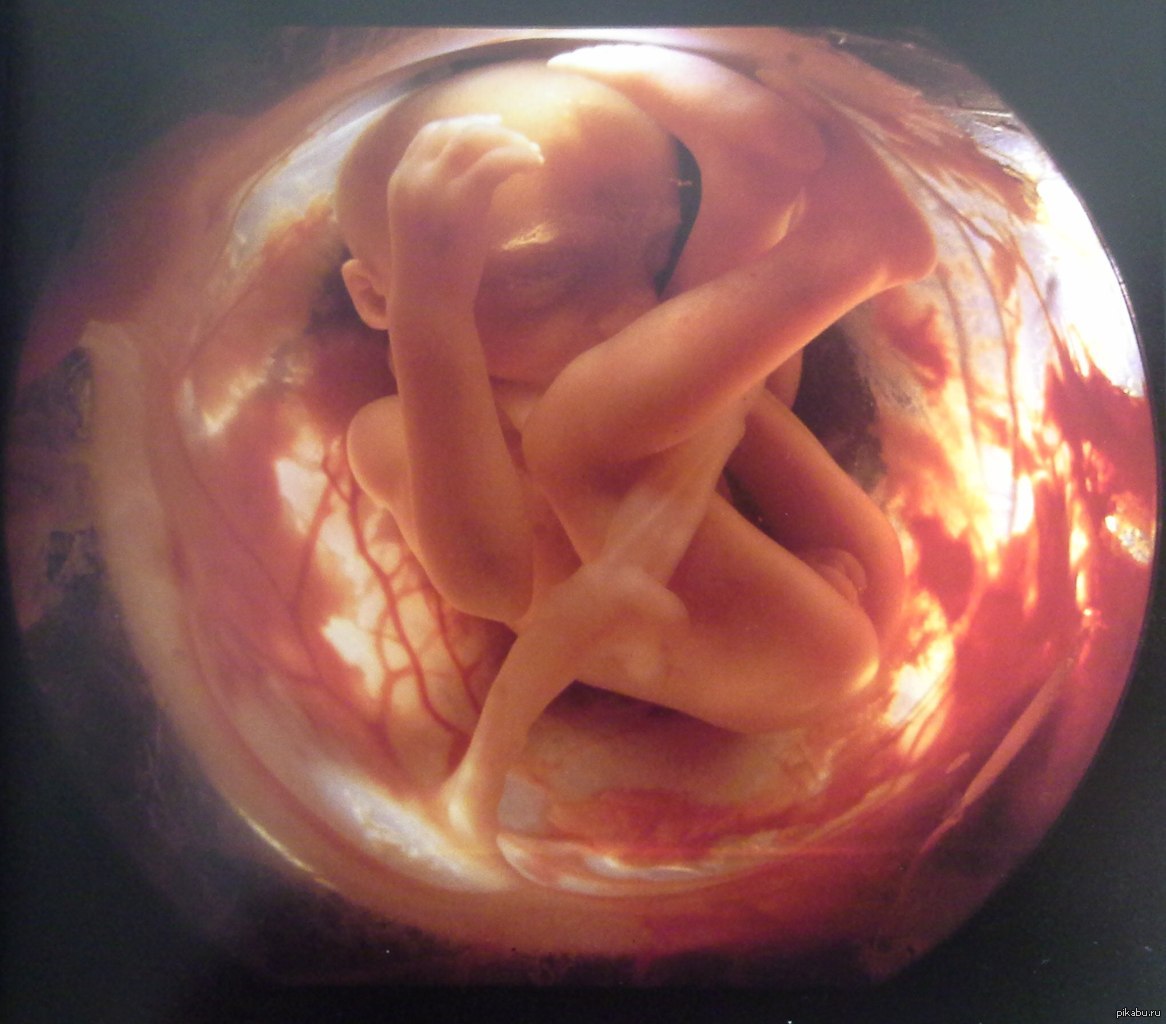

Фотография Плода В Животе

Фотография Плода В Животе 113 фотографий